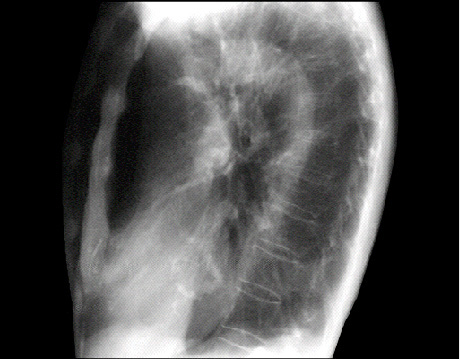

The lateral view is often best for seeing a calcified mitral valve annulus. The “J” shaped density is well seen here, as it does not overlap bony structures.